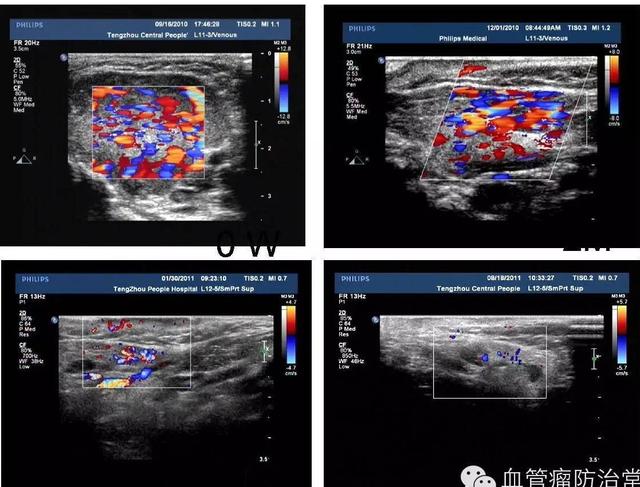

(4月女嬰,腮腺部巨大血管瘤,因生長快形成潰瘍。口服心得安治療3周內潰瘍愈合。隨訪患兒到4歲,無復發,血管瘤體及彩超血流信號全部消退)

對就診時瘤體較大或者口服心得安不能控制的血管瘤患兒,采用新型硬化劑聚桂醇瘤體內注射治療,便可治愈大多數血管瘤患兒。該方法無創傷,無明顯并發癥。我院在國內較早開展超聲引導下硬化劑注射治療血管瘤,明顯縮短了治愈時間,減少了治療費用。